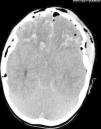

Datos complementarios: estradiol: 28pg/ml(< 10pg/ml), test LH-RH con patrón puberal: FSH (0min): 5 mU/ml (< 1 mU/ml), FSH (20min):13,98 mU/ml (< 1 mU/ml), LH (0min): 1 mU/ml (< 1 mU/ml), LH (20min): 22,13 mU/ml (< 1 mU/ml), ACTH, cortisol, T4 libre, TSH e IGF-I normales. Bioquímica sanguínea, iones, osmolaridad y estudio de orina normales. Edad ósea (Greulich y Pyle): entre 3,5 y 4,2 años. Ecografía pélvica: útero con configuración similar a útero premenárquico y ovarios de 5 cm3 con quistes foliculares. En la RM cerebral se observa encefalomalacia macroquística postraumática con afectación hipotalámica (fig. 2). Se diagnostica de PPC secundaria a TCS. Iniciamos tratamiento con análogos de gonadotropinas (triptorelina: 0,2mg/kg im cada 28 días), consiguiendo una evolución satisfactoria.